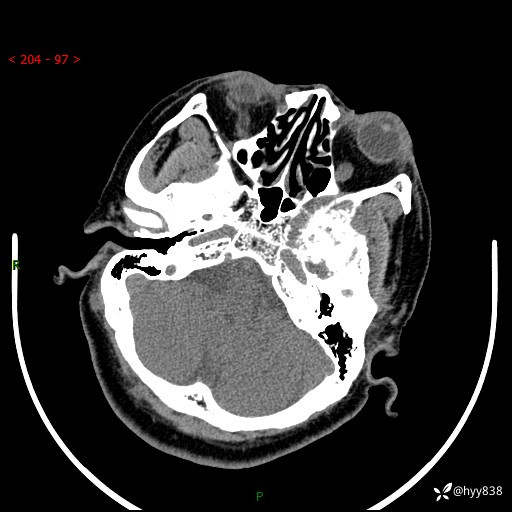

颅脑CT平扫